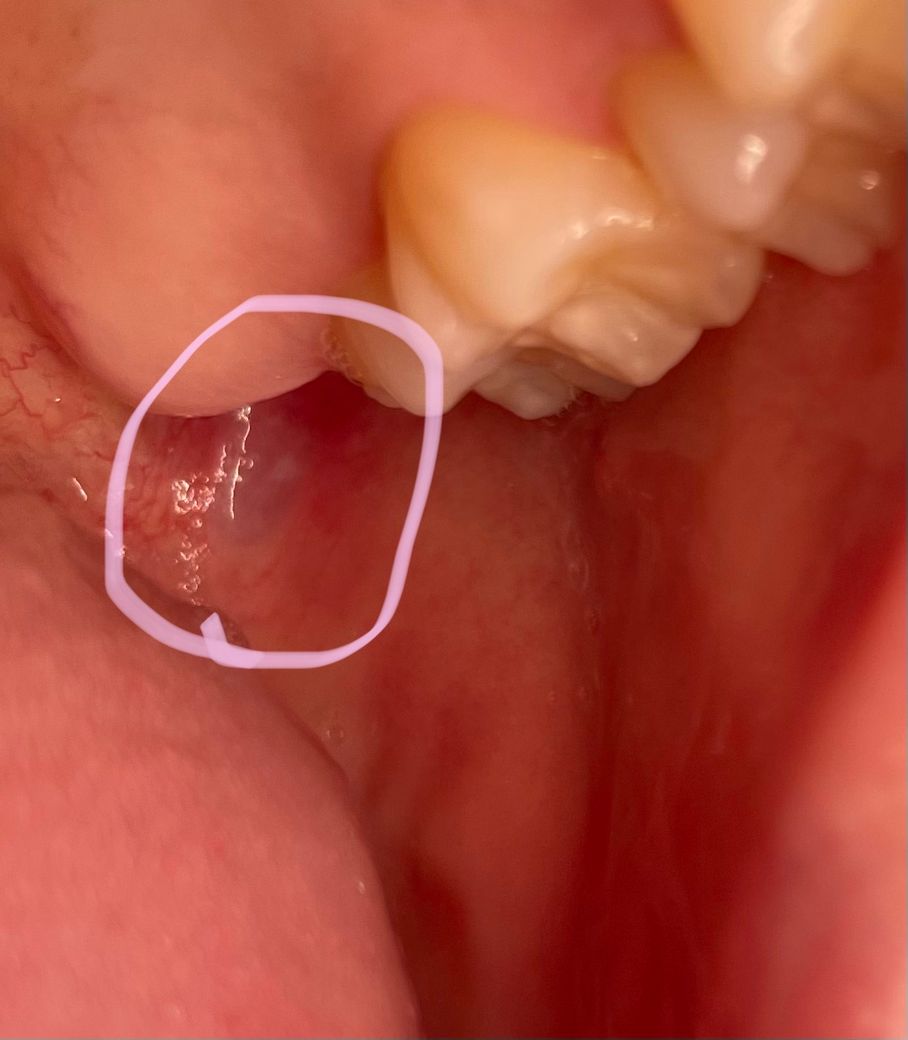

안녕하세요 제가 작년 8월달에 면역력이 너무 떨어져서 입 안쪽에 구내염이 하나 심하게 나서 3개월은 아팠습니다 그 뒤로 통증은 없어지고 알보칠을 많이 발라서인지 저렇게 하얀 궤양흉터가 남았어요

근데 요즘도 질긴고기를 많이 씹거나 달달한 걸 많이 먹거나 이를 오랫동안 안 닦은 날 저 궤양 근처가 동그라미 친 것처럼 빨개지고 약간 사랑니 날때 붓고 쿡쿡쑤시는? 작년에 저 구내염 났을때의 느낌이 나더라고요 저 궤양 이후로 다른 궤양이 난 적은 없는데 왜 저러는 걸까요 배체트병은 아니겠죠...?